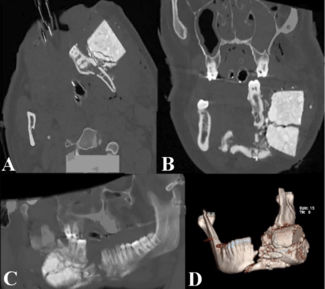

A 23-year-old man presented after a mortar misfired and propelled the ignited aerial shell of a firework toward his face, becoming lodged in his left jaw.